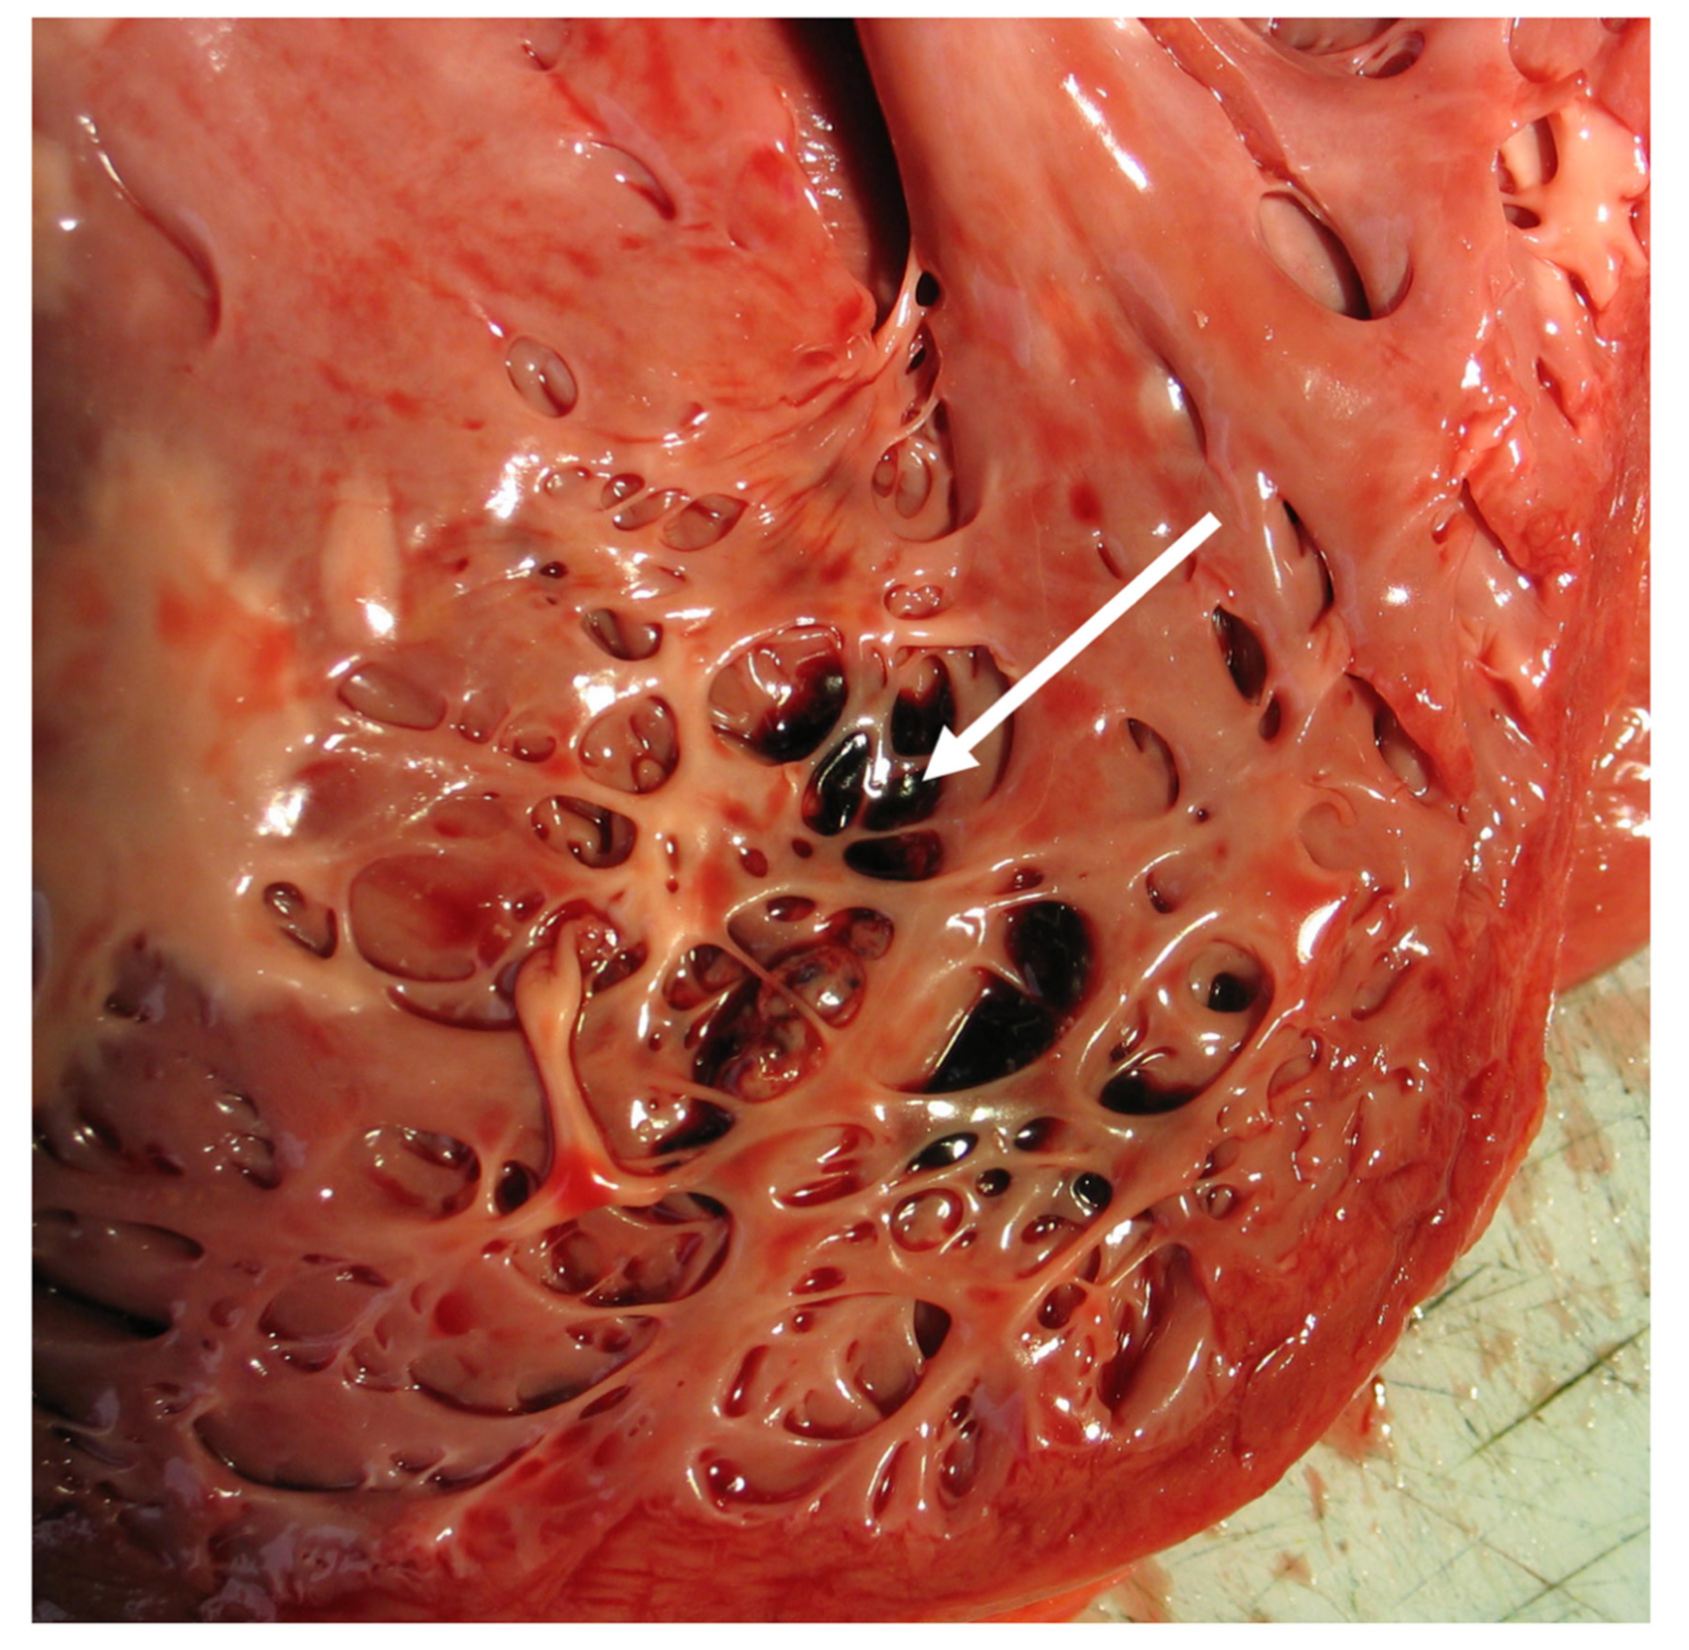

- Boyd, M.T.; Seward, J.B.; Tajik, A.J.; Edwards, W.D. Frequency and location of prominent left ventricular trabeculations at autopsy in 474 normal human hearts: Implications for evaluation of mural thrombi by two-dimensional echocardiography. J. Am. Coll. Cardiol. 1987, 9, 323–326. [Google Scholar] [CrossRef]

- Stöllberger, C.; Finsterer, J. Left ventricular hypertrabeculation/noncompaction. J. Am. Soc. Echocardiogr. 2004, 17, 91–100. [Google Scholar] [CrossRef]

- Burke, A.; Mont, E.; Kutys, R.; Virmani, R. Left ventricular noncompaction: A pathological study of 14 cases. Hum. Pathol. 2005, 36, 403–411. [Google Scholar] [CrossRef] [PubMed]